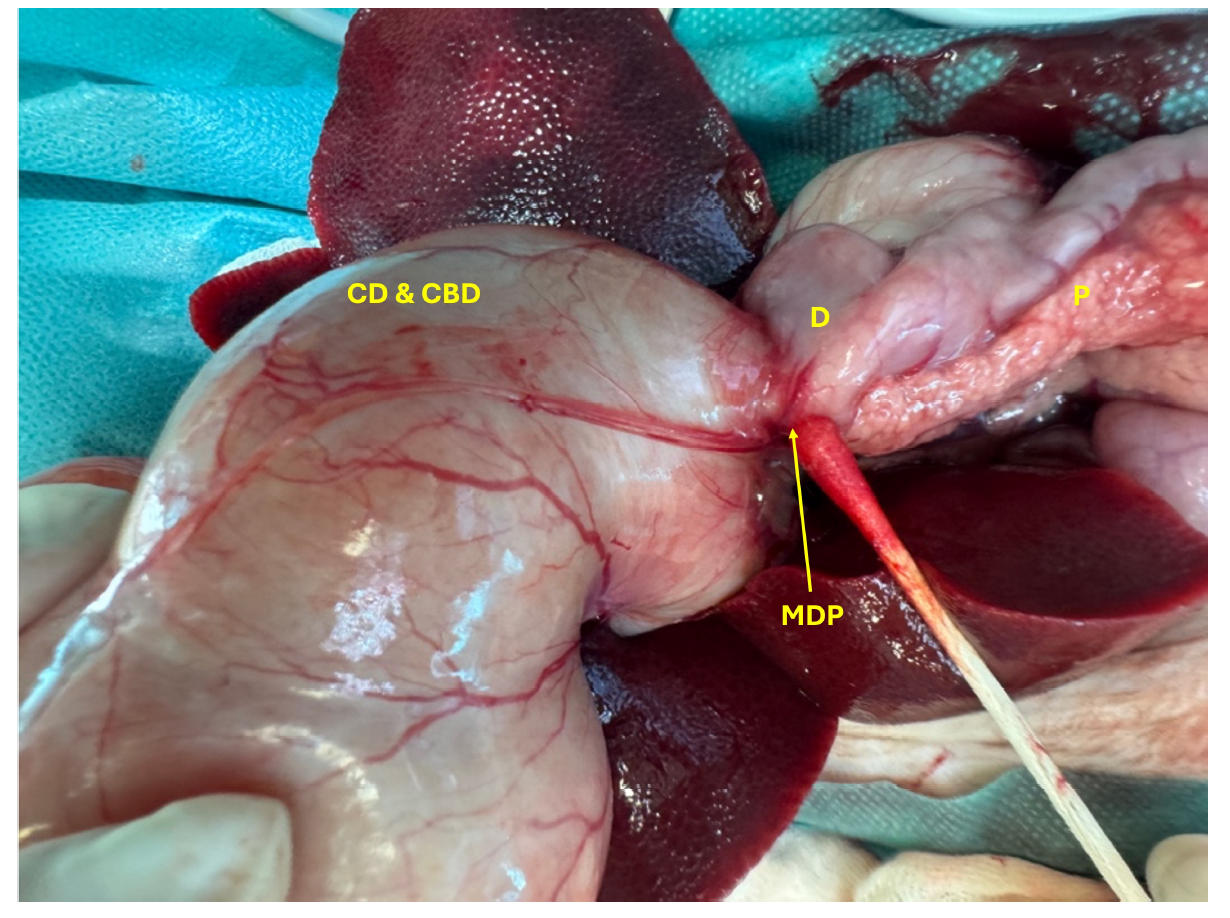

腹部探查显示胆囊和胆总管显著扩张,大小约为10×7厘米,肝管平均直径约8毫米(下图)。胆囊、胆囊管和胆总管的解剖结构已无法区分。

↑ 扩张的胆囊(GB),增大的胆管(CD)和胆总管(CBD)进入十二指肠(D),严重扩张的肝管(HD)和严重炎症的胰腺(P)。

此外,胆总管与十二指肠在十二指肠乳头水平的连接处严重扩张(下图)。

↑ 胆管(CD)和胆总管(CBD)与十二指肠(D)在十二指肠乳头(MDP)处的连接严重扩张,以及炎症的胰腺(P)。